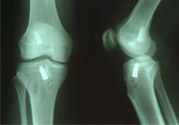

1、部分斷裂:關(guān)節(jié)內(nèi)無積血,外翻位X線片顯示內(nèi)側(cè)關(guān)節(jié)間隙不大,可做局部封閉、彈性繃帶加壓包扎,早期鍛煉股四頭肌或用踝上長腿石膏托固定于膝內(nèi)翻和稍屈位3—4周,石膏完全干后可開始股四頭肌鍛煉和下地行走。

2、完全斷裂:原則上應(yīng)行手術(shù)治療如韌帶斷裂,可直接縫合;如骨附著處撕脫,可用鋼絲貫穿法固定或直接縫合于骨膜及軟組織上。如有撕脫骨片,則用鋼絲或螺絲釘固定。如合并半月軟骨損傷,應(yīng)予以切除。合并前膝交叉韌帶損傷者,應(yīng)先修補。術(shù)后石膏固定4—6周。

4、膝交叉韌帶損傷:前交叉韌帶合并脛骨棘撕脫骨折者,可用膝過伸和后推脛骨使之復(fù)位,用長腿石膏固定4—6周。對于未能復(fù)位者,應(yīng)及時手術(shù)修補。將骨折片用鋼絲固定。單純韌帶斷裂者,用石膏固定。對陳舊性損傷,以保守治療為主,經(jīng)鍛煉后,關(guān)節(jié)仍不穩(wěn)定,亦可考慮手術(shù)修補。后交叉韌帶可不修補。